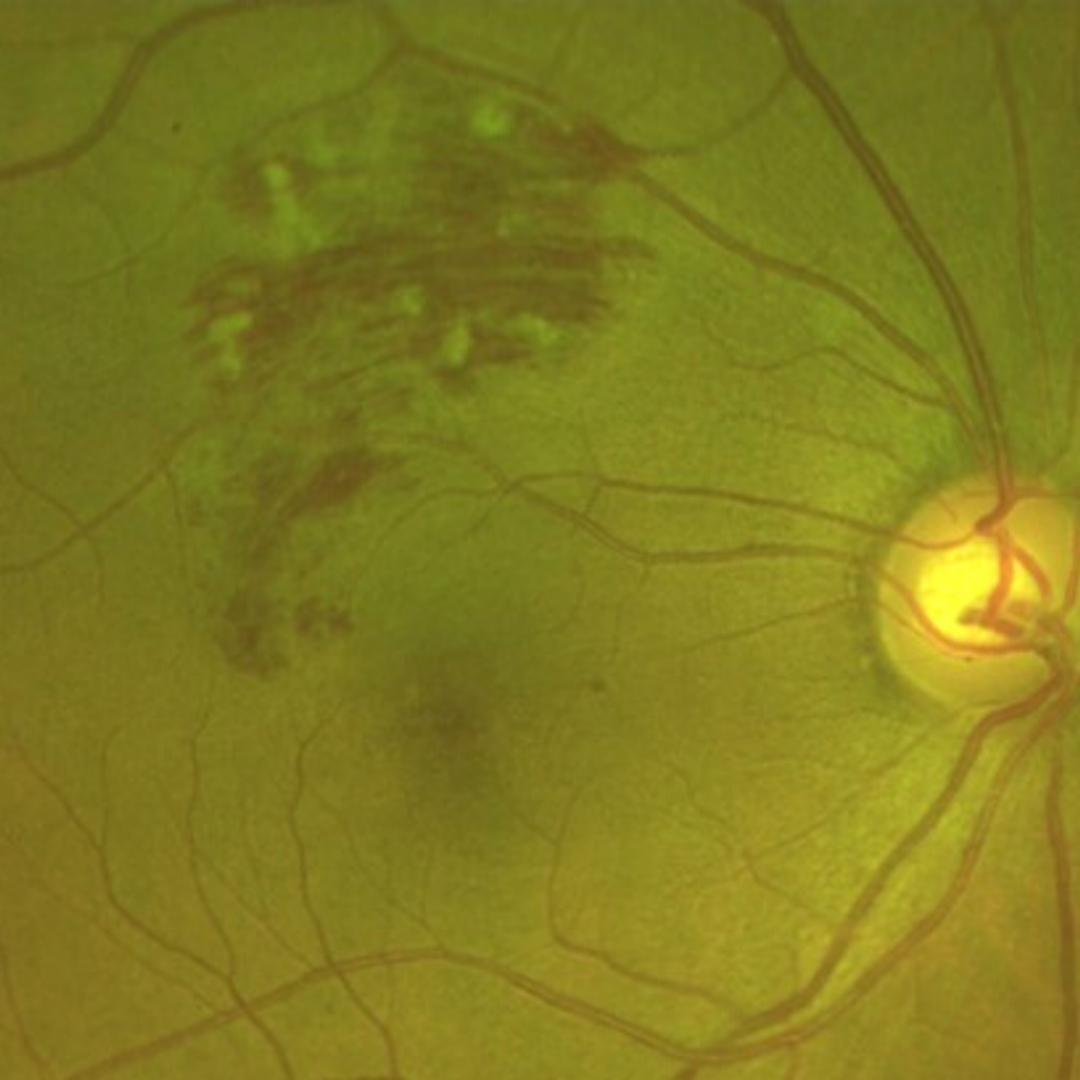

The clinical appearance of retinal vein occlusions change over time. Acute presentations are characterised by widespread retinal haemorrhages, including blot, dot and flame haemorrhages.

Cotton wool spots may be present, as may retinal or macula oedema (this is covered in more depth further down this page).

Central retinal vein occlusions also have an associated elevation of the optic nerve head.

Over time, the retinal haemorrhages associated with an acute venous occlusion are reabsorbed. Macular oedema may persist and other vascular changes can occur, including the development of either collateral vessels or neovascular vessels.